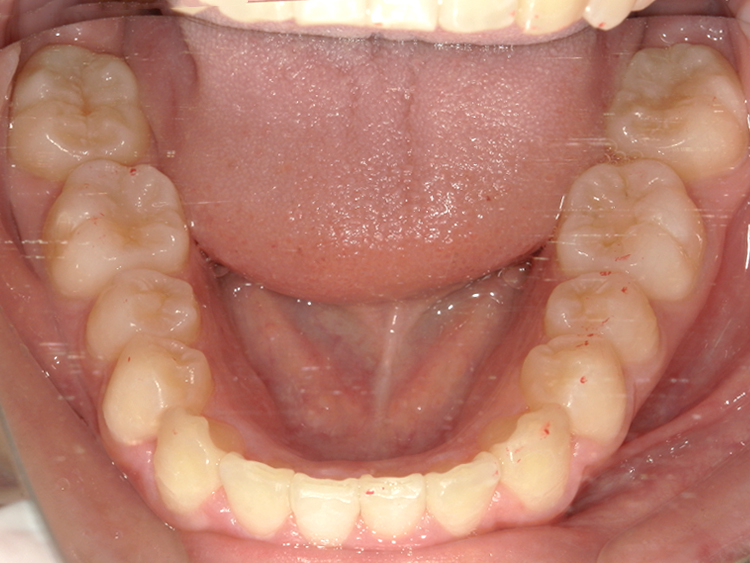

Before

After

| 主訴 | 上下の歯のガタガタを治したい |

|---|---|

| 年齢 | --- |

| 治療 期間 |

約10ヶ月 |

| 治療 内容 |

インビザラインiGoで上下顎の治療。 狭まっていた歯並びを広げることで、 ガタガタに並んでいた歯を綺麗に並べた。 |

| 治療費 | ¥517,000(税込)+月額調整料 |

| 治療のリスク | 歯と歯の間を削ることでスペースを確保するので、 場合によっては歯が染みる症状が出ることがある。 |